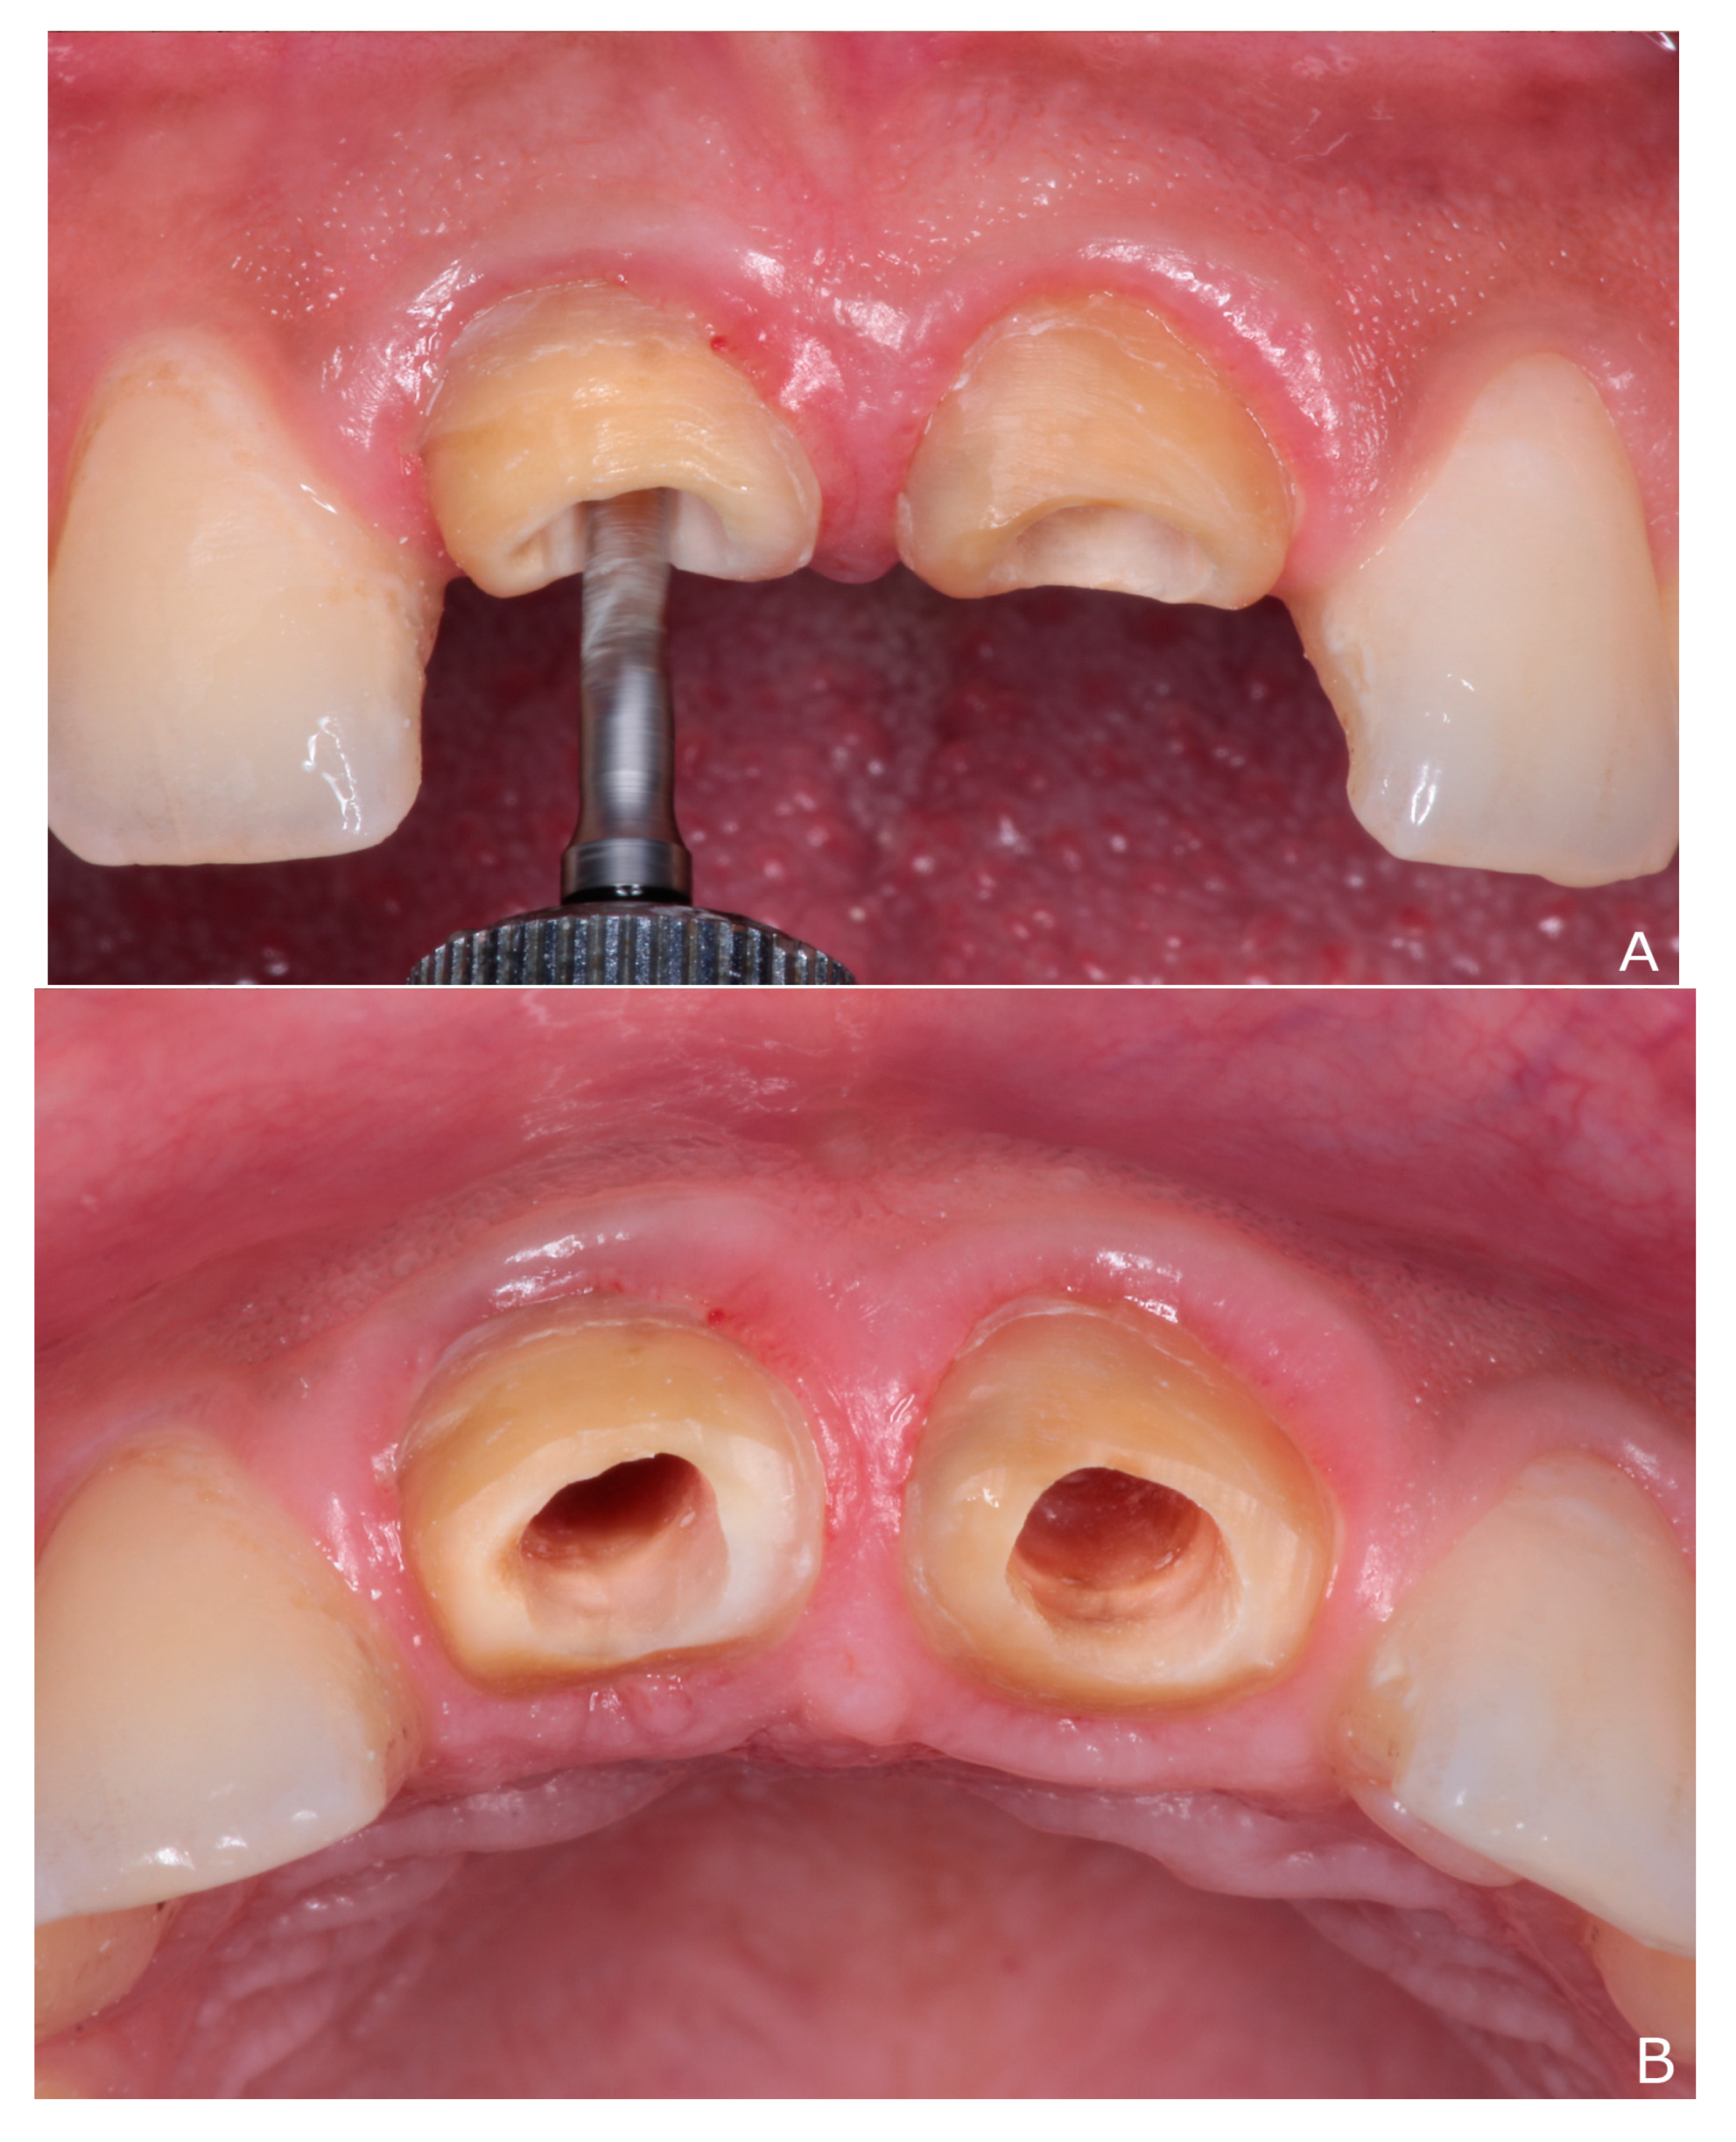

2. Clinical Report